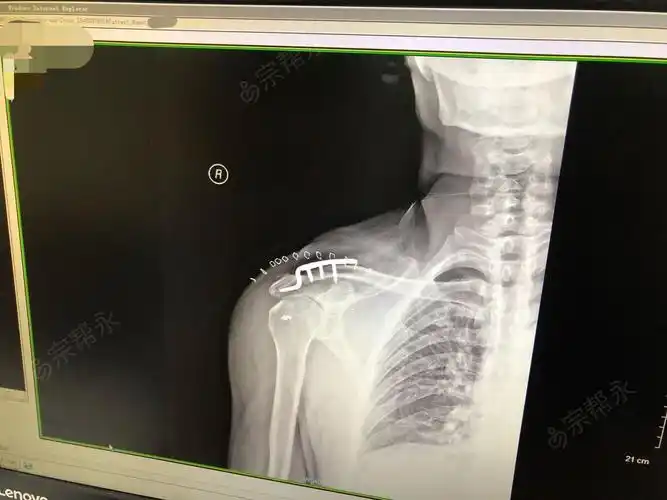

肩锁关节脱位Ⅲ型喙锁韧带重建手术